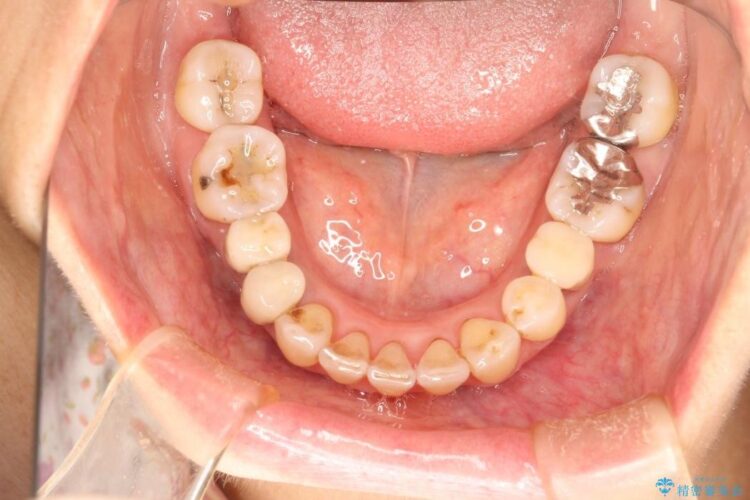

【50代女性】八重歯のインビザライン矯正 治療例

八重歯の改善を希望され来院されました。

当初はセラミックでの治療を希望されていましたが、噛み合わせと歯並びを治していく為に矯正治療を提案させていただき、インビザラインでの矯正を行う計画にしました。

頻繁にご来院いただく事が難しかったこともあり、型取りのし直し(リファインメント)を2回行いました。時間はかかってしまいましたが、患者様には大変ご満足していただくことができました。